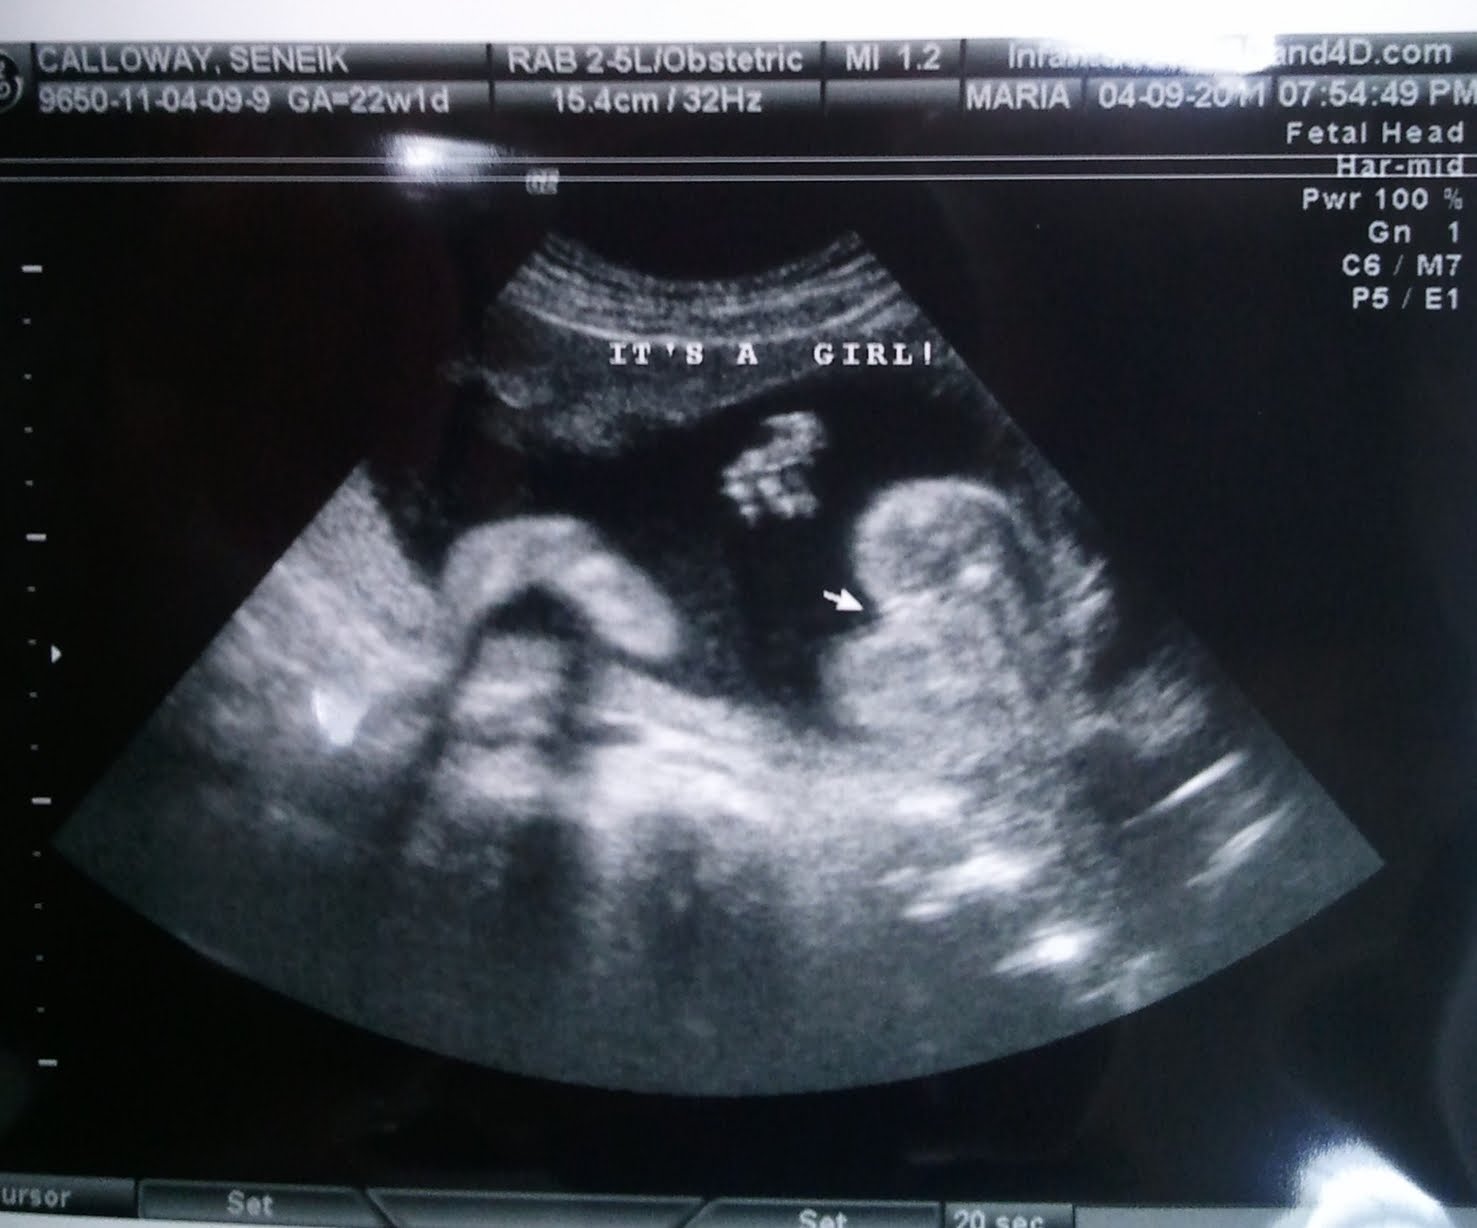

We just found out last night on the second attempt (first time baby had its legs crossed)that IT's A GIRL! We will be naming her Xochitl Calloway. Xochitl is pronounced Xochitl (So-Cheel).

Confirmation...It's a Girl! ----> 22 weeks